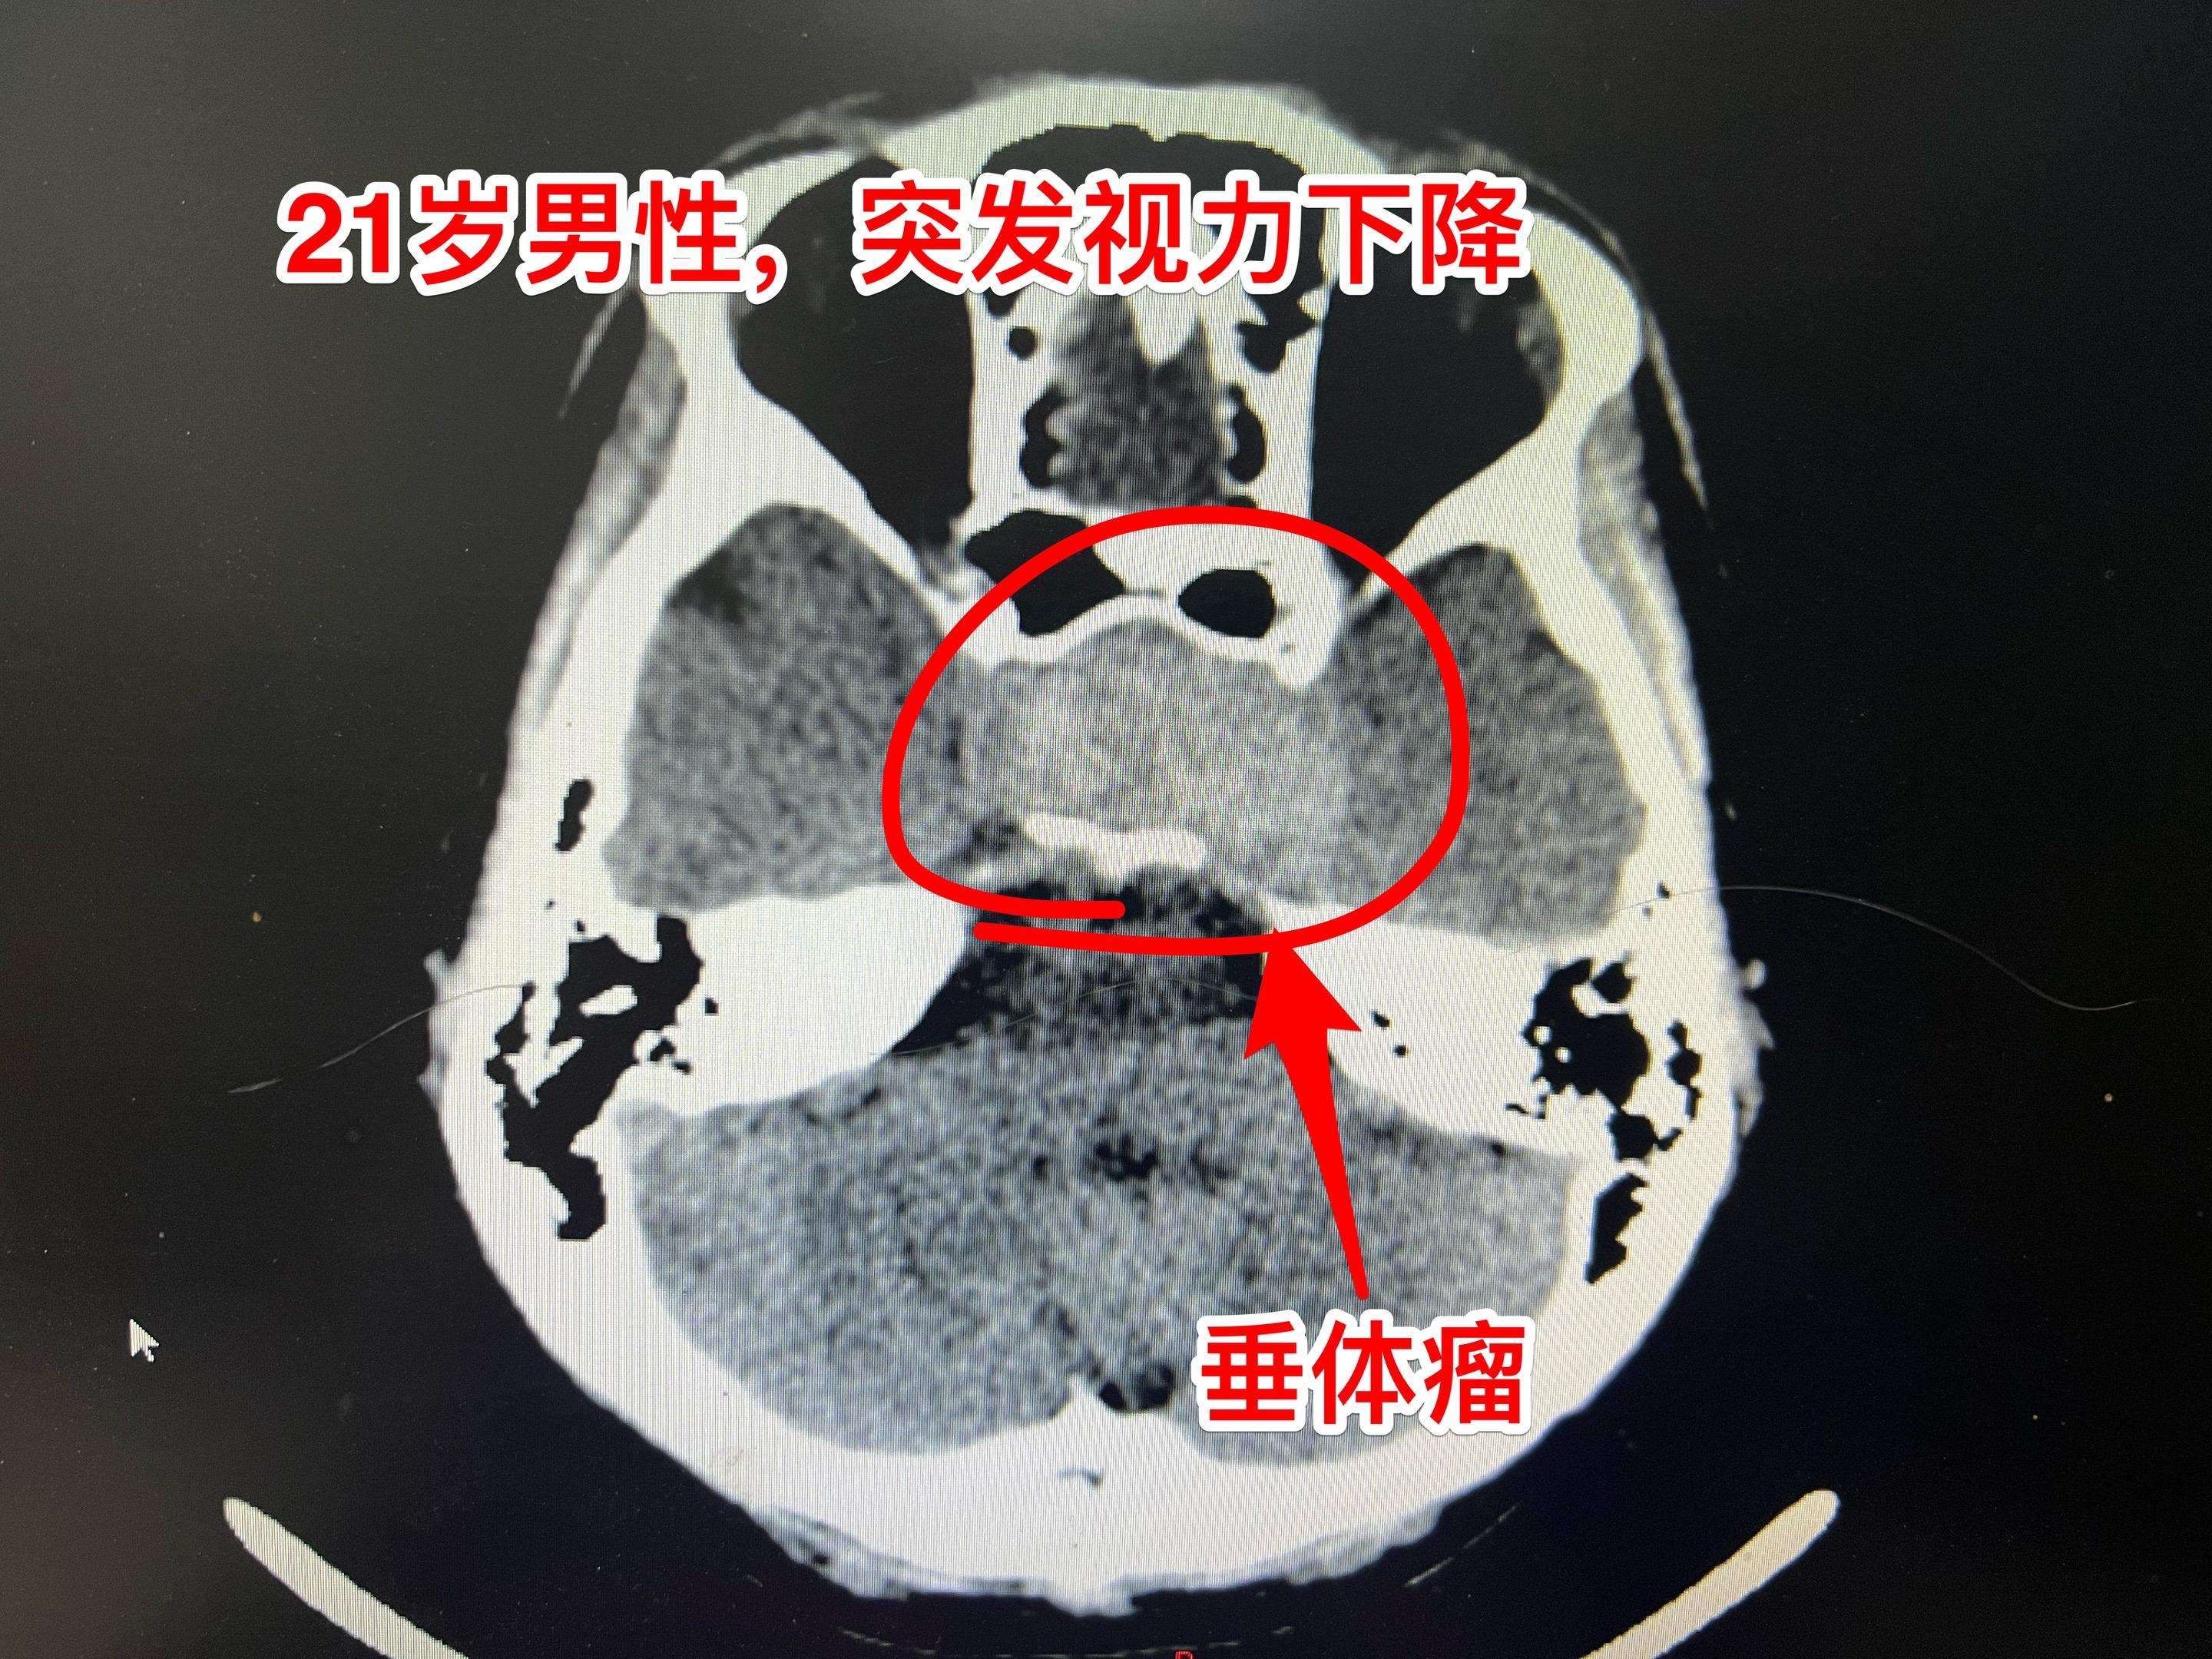

两个月内两个垂体瘤卒中 病例 垂体瘤卒中的最明显的症状是突发视力下降...

垂体瘤卒中,女教师6月12日突发视力下降。48岁定州市女教师6月12日...